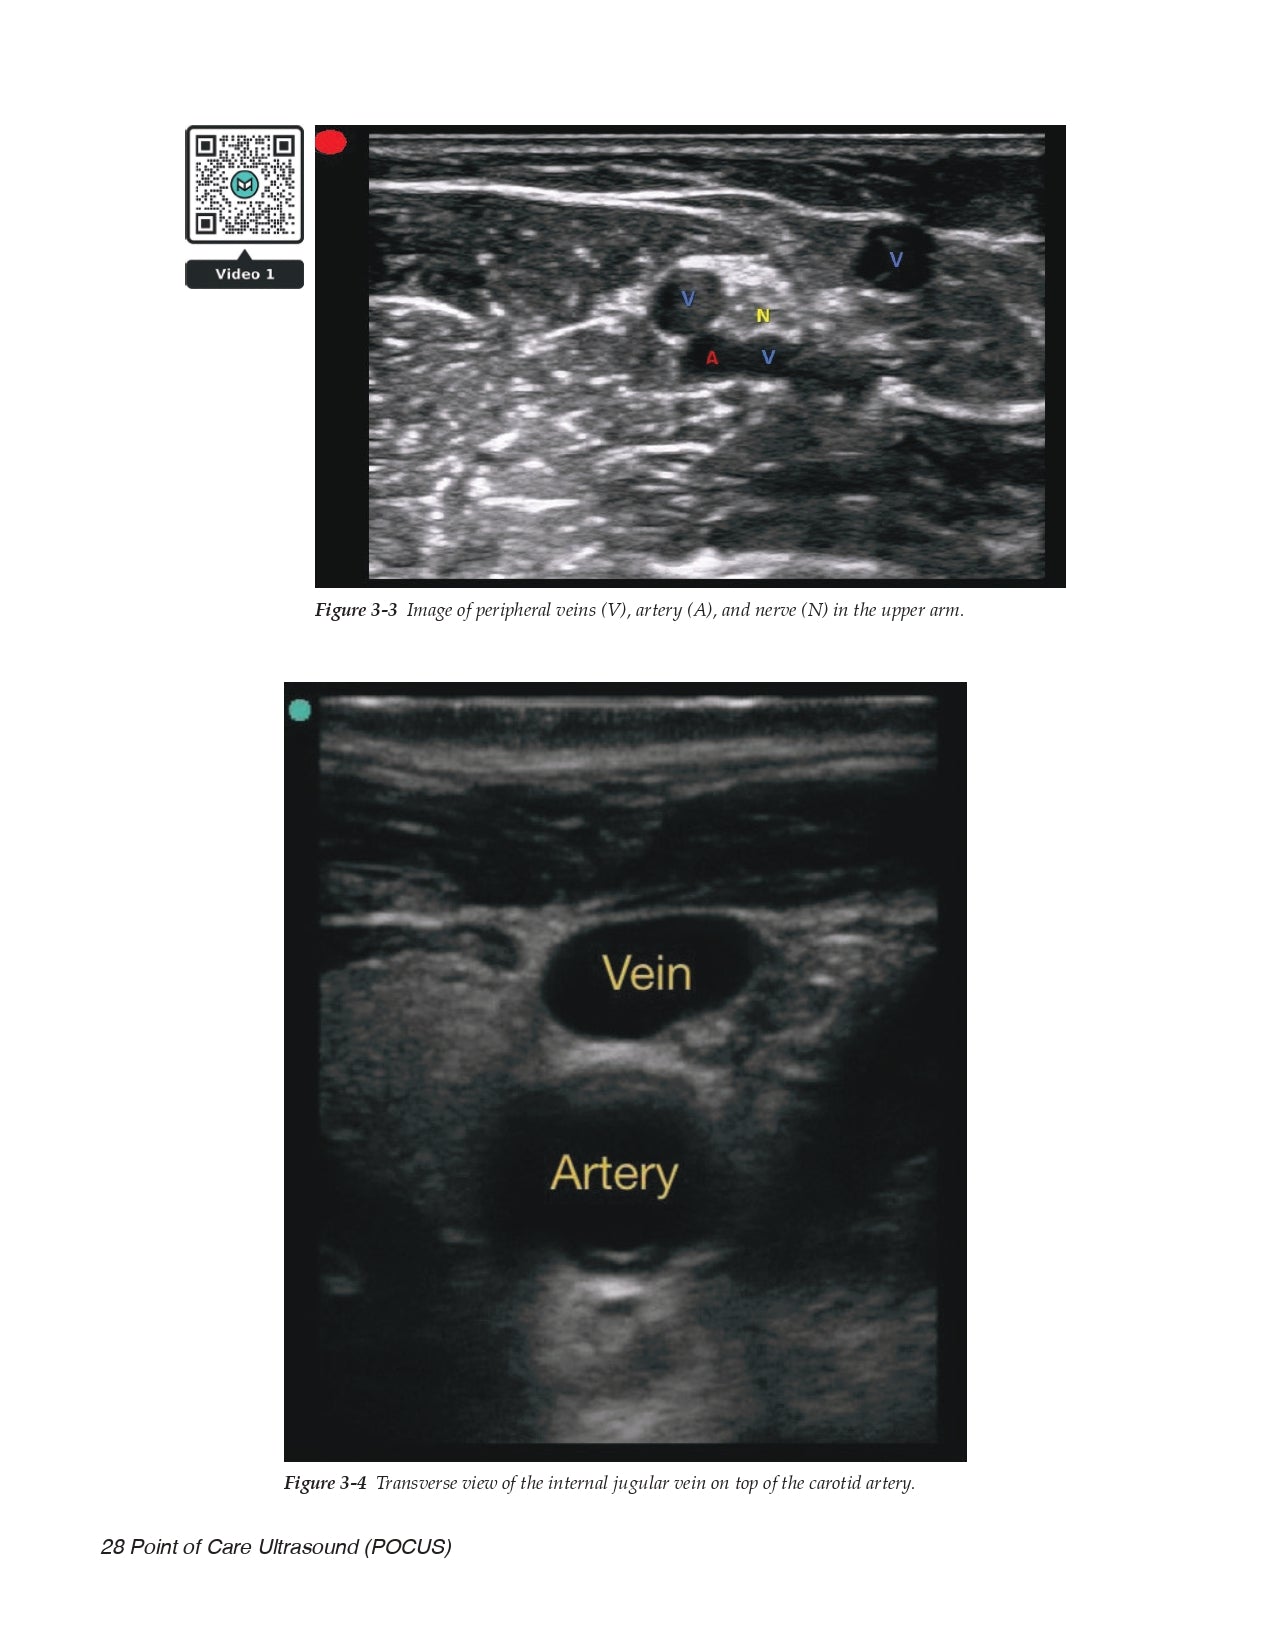

- Vessel Location for Catheter Placement